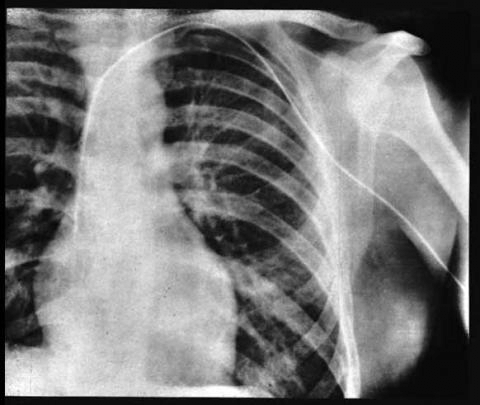

1956년 노벨 생리의학상 수상자 Werner Forssmann

업적: 심장카테터법 개발

본인 팔 정맥에 관을 꼽고 그 관을 계속 집어넣어 심장에 도달한 공로로 노벨상을 받음.

포르스만이 직접 찍은 x레이 사진

팔에서 심장으로 가는 관이 보일거임